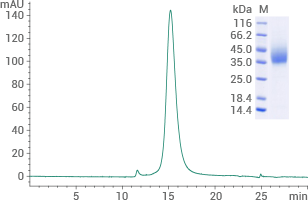

Human THR-β protein (His Tag): (Cat#: 15737-H07E) HPLC verified

Image Credit: Sino Biological Inc.